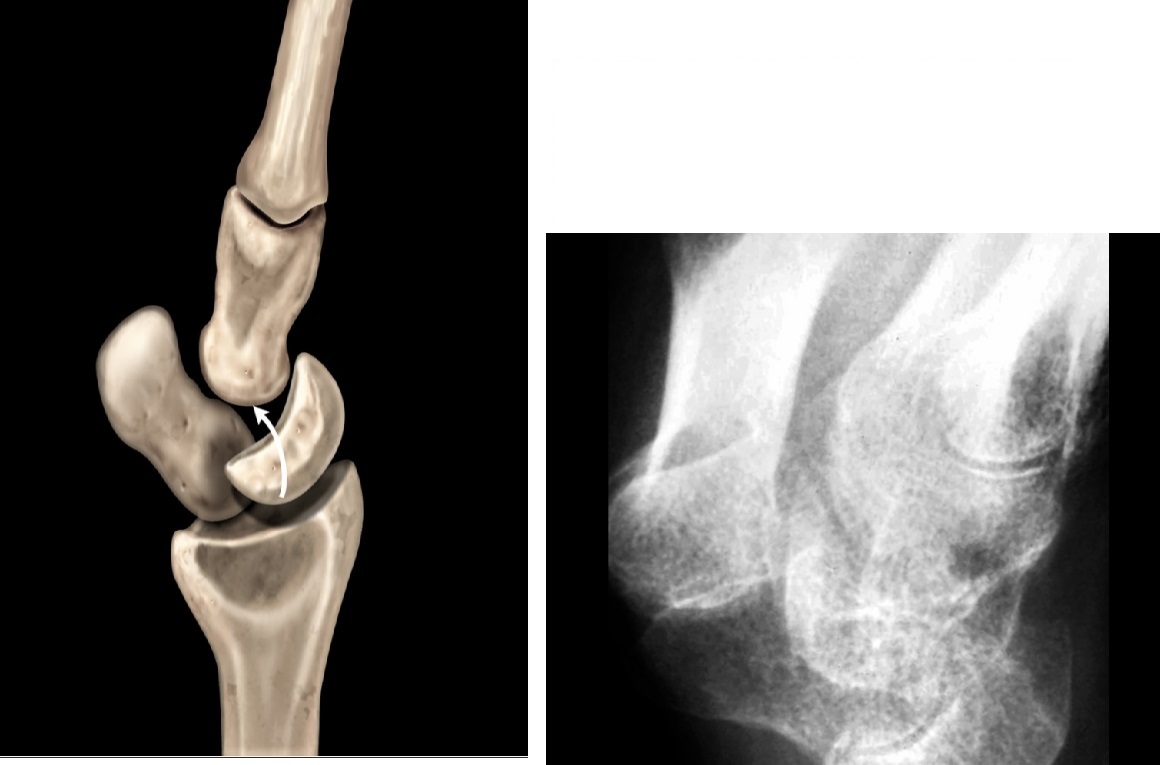

Bennets

Fracture base of the first metacarpal

Pull of the abductor pollicus longus (APL tendon causes dorsolateral dislocation

Nb a comminuted # base of 1st metacarpal = ROLANDO

Gamekeepers

Avulsion fracture of the base of the proximal first phalanx

Ulnar collateral ligament disruption

STENER lesion = when adductor tendon gets caught in the torn edges of the UCL = Surgery